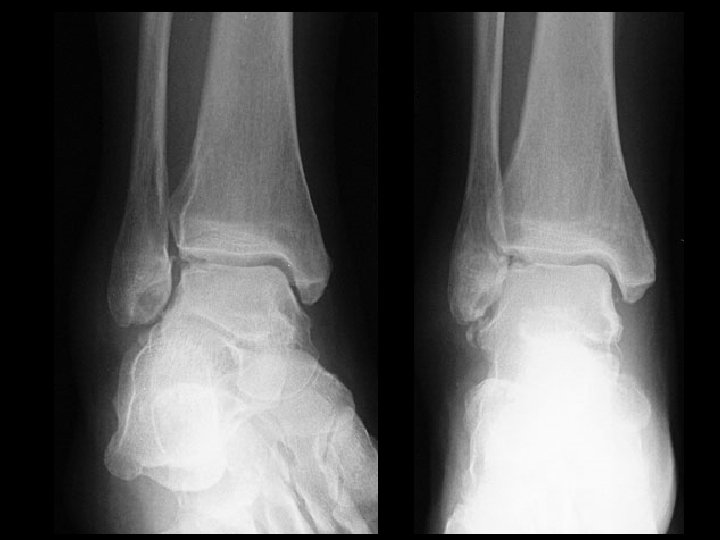

Talar osteochondral fracture • Findings: – Cortical irregularity of the lateral talar dome with bony fragments in the lateral mortise and widening of the distal tibiofibular syndesmosis – Check for proximal fibula fracture • ddx: – NONE! – This is an Aunt Minnie!